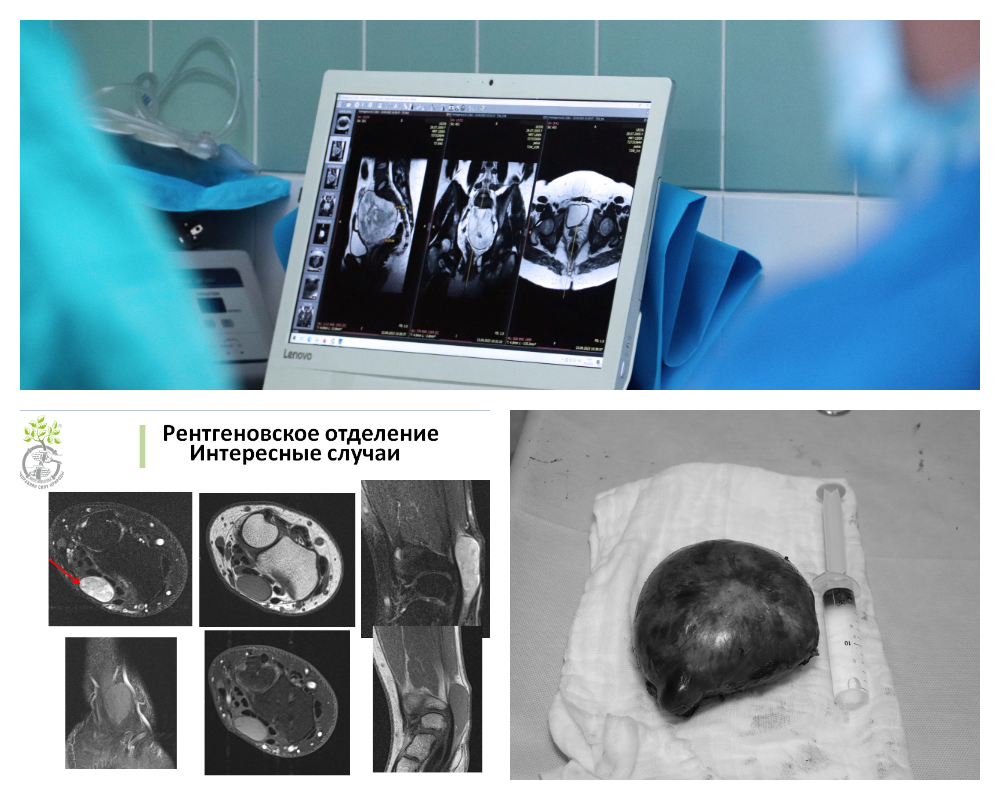

Недавно врачами-рентгенологами Центра Илизарова было проведено обследование 19-летнего юноши, у которого выявили несколько новообразований в грудном отделе. Во всех этих опухолях было выражено накопление контрастного вещества.

Учитывая большой клинический опыт в данном направлении, рентгенологи при постановке диагноза склонялись к множественным шванномам на фоне нейрофиброматоза II типа. Пациенты с данным орфанным заболеванием не раз проходили лечение ортопедических осложнений в отделениях Центра Илизарова.

- То, что мы видим, на 60-70 % у молодого пациента идет перекрытие спинно-мозгового канала данными новообразованиями, деформация спинного мозга, походка нарушена. Пациенту даны рекомендации обратиться к нейрохирургам Центра Илизарова и генетикам для консультации и дальнейшего оперативного лечения, - рассказал заведующий рентгеновским отделением Центра Илизарова, д.м.н. Константин Дьячков.

Подобные пациентские истории с диагностикой и лечением шванном и их последствий были в Центре Илизарова в 2023 и 2024 годах. В одном случае новообразование было обнаружено с помощью магнитно-резонансной томографии у пациента в лучезапястном суставе.

Во втором случае нейрохирургами Клиники патологии позвоночника и редких заболеваний и врачами Курганского онкологического диспансера у 18-летней пациентки была удалена гигантская шваннома корешка спинномозгового нерва с прорастанием в область малого таза. Как раз это был тот самый случай неожиданной находки на профосмотре перед устройством на работу.